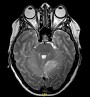

Adult-onset Lhermitte-Duclos disease (LDD) is a rare disorder, with a prevalence of < 1/1000000, characterized by slowly growing cerebellar hamartoma (dysplastic gangliocytoma) and was recognized to be one of the Cowden syndrome (CS) pathognomonic criteria since 2004. The clinical picture of LDD is associated with the enlarging tumor in the posterior cranial fossa, resulting in cerebellar dysfunction and raised intracranial pressure. Sometimes the patients complain of headache and mild instability only, but vomiting ataxia and dysarthria may also occur.A 43-year-old women, with a past history of breast cancer and thyroid structural lesions, was admitted in the emergency department of our institution after an accidental fall causing head trauma in the occipital region. A Computed tomography (CT) scan of the head showed low-density mass in the left-superior cerebellar hemisphere. She was otherwise asymptomatic. She was eventually admitted to the neurology department for further evaluation. We performed 3 Tesla Magnetic Resonance imaging (MRI) and spectroscopy showing a lesion of the left cerebellar hemisphere, with the characteristic «tiger-striped» appearence on T2-weighted image (T2WI) and slightly compressing fourth ventricle. No enhancement after gadolinium administration was observed neither significant modifications in the ratio of metabolites at spectroscopy were noticed compared with healthy controlateral parenchyma. Cerebral angiography confirmed that the lesion was poorly vascolarized. Clinical history and MRI imaging are highly suggestive and specific for a definite diagnosis of CS. Furthermore, optical coherence tomography (OCT) and fluoroangiography revealed an exudative maculopathy with choroidal neovascularization that was never described before neither with LDD or Cowden syndrome. Genetic testing detect germline mutation c. 204C > G, p.Tyr68* of PTEN tumor suppressor gene present on chromosome 10q23.3 confirming the diagnosis of CS. At 3, 6 and 12 month MRI follow-up the lesion remain stable and the patient is still asymptomatic.

Figure 1. T2WI, Gd+ T1WI and Spectroscopy at the time of diagnosis